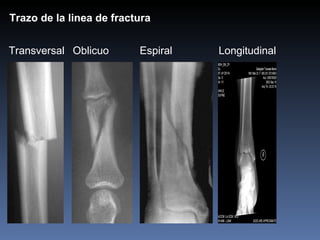

Transversal   Oblicuo  Espiral   Longitudinal Trazo de la linea de fractura